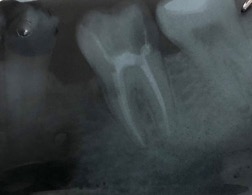

Una corretta terapia canalare con un perfetto sigillo a livello degli apici delle radici è fondamentale. I denti devitalizzati impropriamente possono creare ulteriori problemi che poi andranno a ripercuotersi sulle cure effettuate successivamente come le ricostruzioni e le corone protesiche con conseguente fallimento del piano terapeutico.

Capita spesso di incontrare denti già devitalizzati in maniera impropria che necessitano, seppur asintomatici, di essere ritrattati per evitare che i granulomi infetti visibili radiograficamente si evolvano riassorbendo tutto l’osso sottostante.